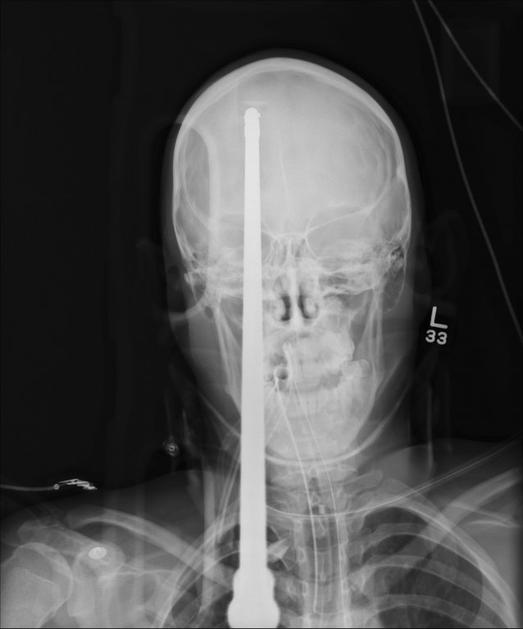

Glavo mu je preluknjala harpuna

Yasser Lopez